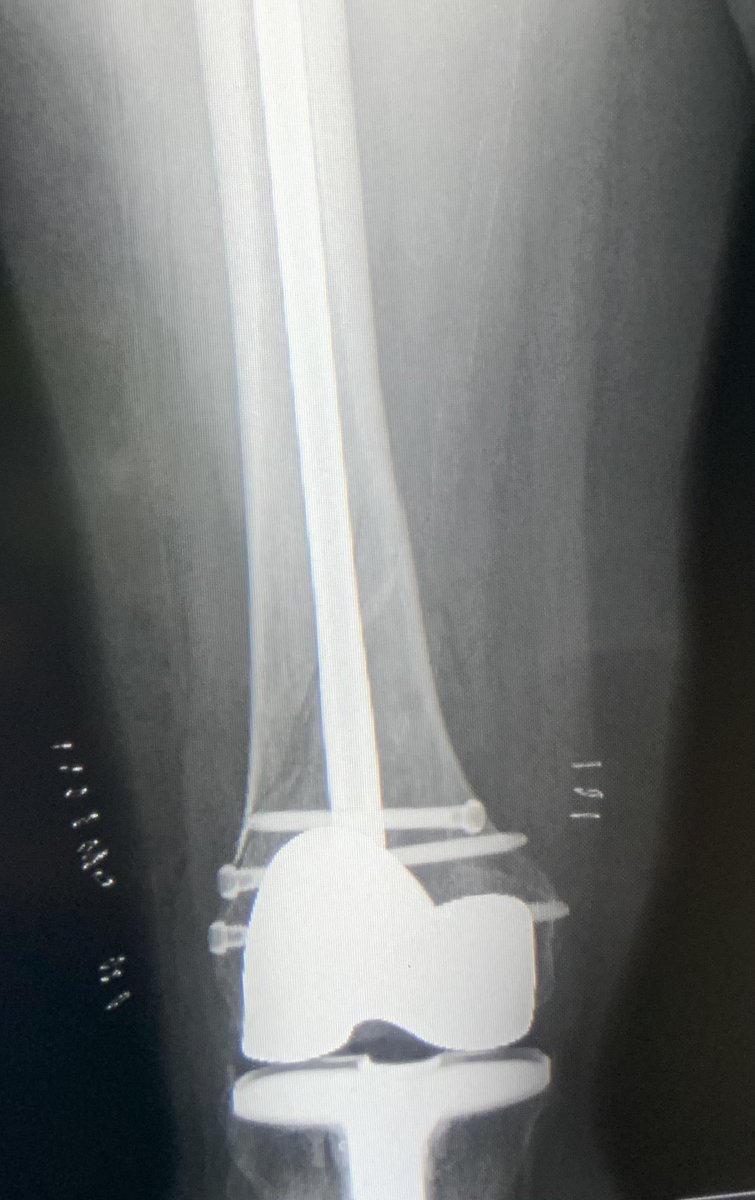

[4/5] Clamp then stayed on the entire time and retrograde nail went in. Here I am forced into posterior starting point which I knew would give me a slight malreduction problem in the end; I aimed to minimize that by keeping the clamp on until nail was locked proximal and distal.

[5/5] Finals. Looks great on AP, but on lateral we still ended up with a little malreduction because starting point limited. But bone was good and 3 screws in distally, so I was not concerned. If you want a paper about which knees have a posterior start: https://pubmed.ncbi.nlm.nih.gov/24929282/